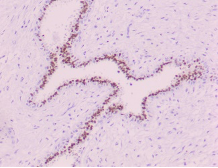

HISTOPATHOLOGY

Fig shows an endoscopic biopsy from a 54 year old individual. Identify the anatomical part of the intestine. What is the pathology. With what clinical symptoms do these patients present? (see surface epithelium)